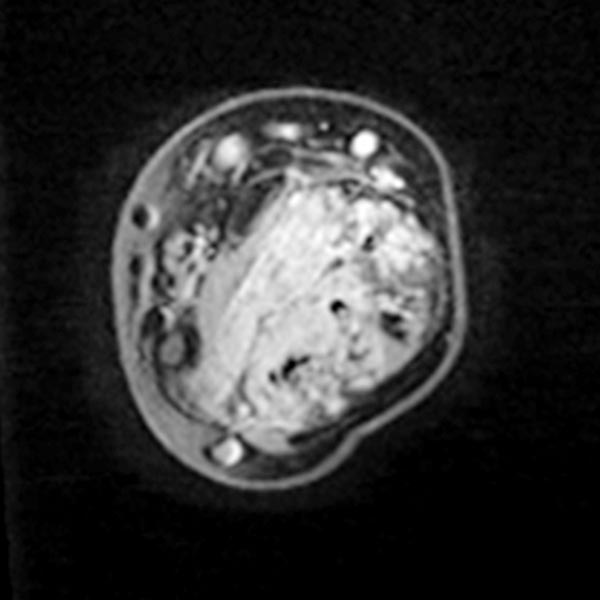

Axial T1-weighted, fat-suppressed contrast-enhanced sequence of the mid-forearm.

The venous malformation accumulates contrast within the involved muscle.

However, the vascular lumina of the venous malformation are relatively small, and no major tubular portions are found.

On account of the relatively small individual vessel diameters of the venous malformation, it is also difficult to puncture them directly. Varicography using a direct puncture technique shows multiple, rather elongated, partly reticular dysplastic small-lumen venous channels.